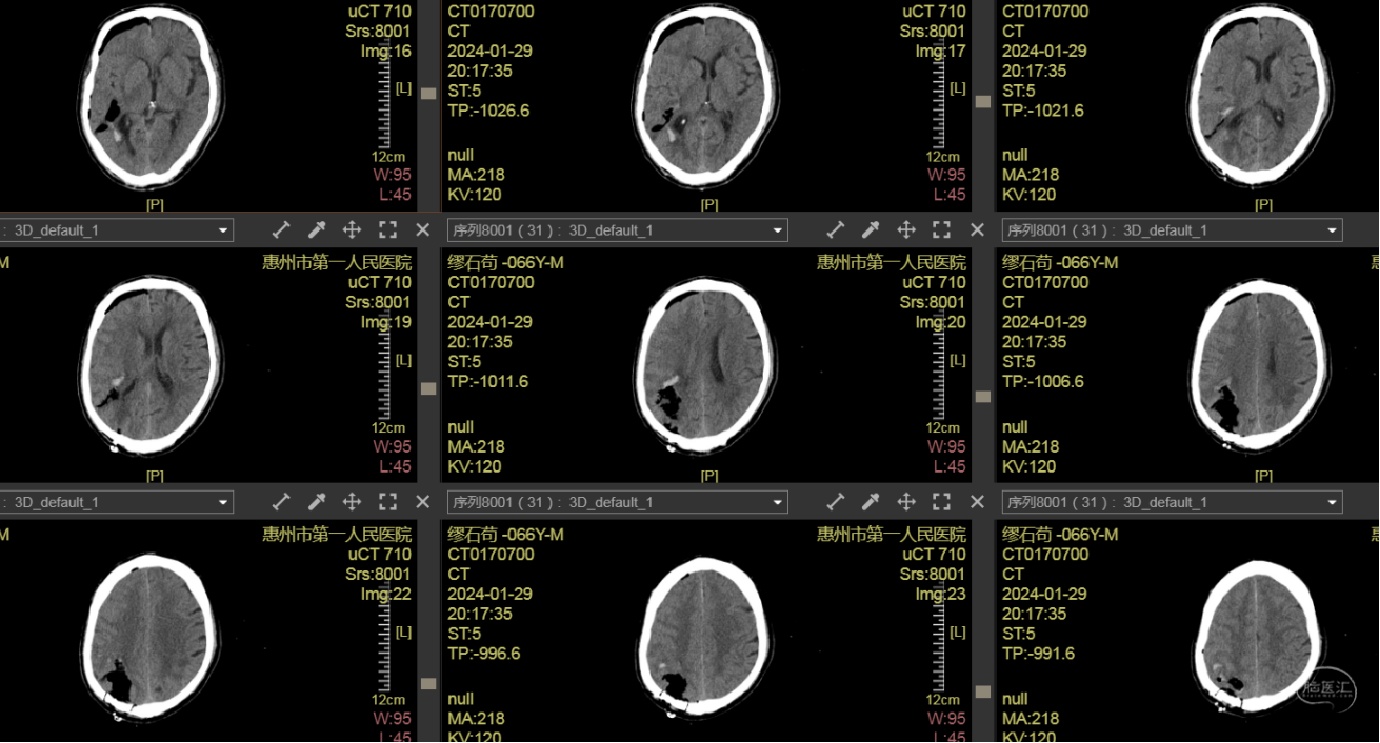

头颅CT示:右侧颞顶枕叶脑出血(78ml),内斑点、小片状持续强化灶,活动性出血?血管畸形?

术前CT

血肿内疑似有血管畸形